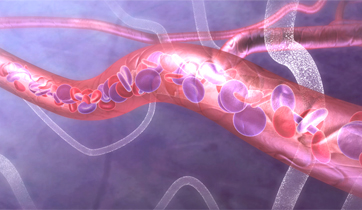

EnCompass F2 Device for cerebral embolic protection system in TAVR procedures

EnCompass Technologies

EnCompass’ F2 filter has pores small enough to block most emboli to the brain while preserving blood flow. During the TAVR procedure, 360-degree wall apposition of the filter in the aortic arch prevents migration. The filter, attached to a self-expanding, nitinol stent, is easy to insert, deploy and retrieve, according to the company. Copyright ©2021 KO Studios.